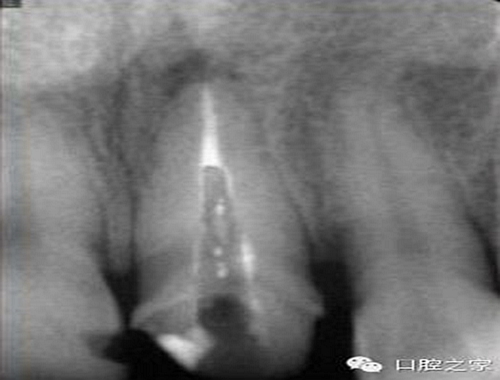

大多數(shù)醫(yī)生在樁道預(yù)備時(shí)習(xí)慣于干燥預(yù)備根管(圖 1),這樣很容易破壞根管壁的牙本質(zhì)結(jié)構(gòu),同時(shí)也可形成較厚的玷污層,影響樹脂水門汀與牙體組織的粘接。因此,臨床操作時(shí)應(yīng)選擇沖洗的方法冷卻預(yù)備根管(圖 2),防止牙膠及封閉劑粘連附著于根管壁形成第二玷污層(根管治療時(shí)形成的玷污層稱為第一玷污層),有利于樹脂水門汀與根管牙本質(zhì)的粘接。

圖1:干燥預(yù)備根管。

圖2:沖洗預(yù)備根管。